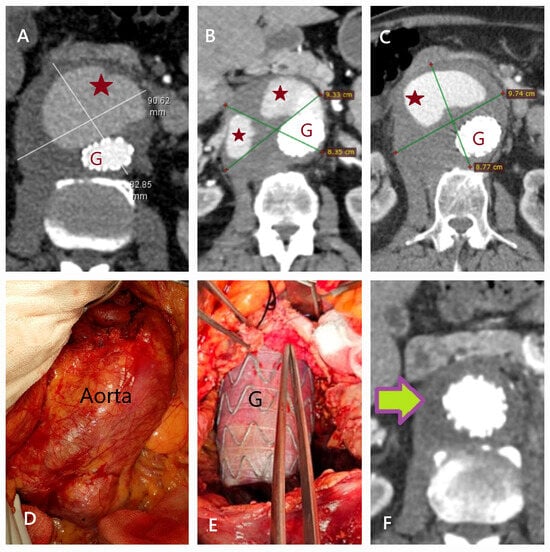

5.1. Failure of EVAR

5.2. Conversion to Open Surgery